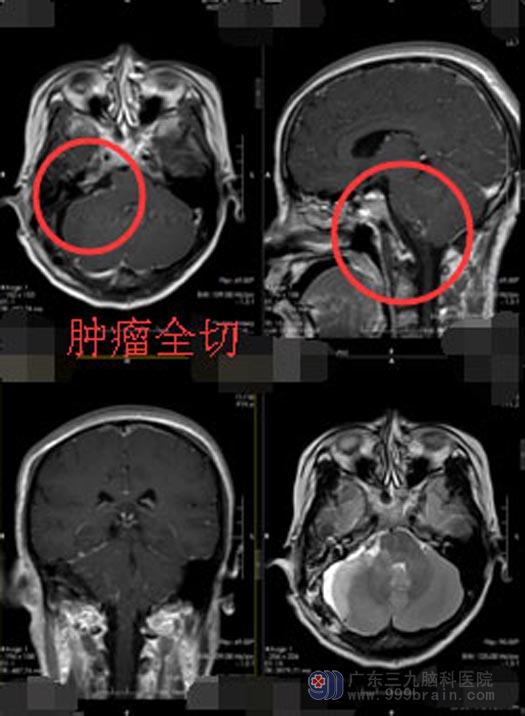

因两个肿瘤长在不同侧,且相距比较远,无法进行一次性切除。右侧桥小脑角区的肿瘤较大,可以先行切除,较小的脑膜瘤等三个月后再进行处理。赵女士及家属知情同意后,由医院副院长、神经外五科主任鲁明主刀在全麻下行“右侧桥小脑角区肿瘤切除术”,显微镜下见右侧听神经、面神经位于肿瘤的前下方,肿瘤与神经黏连非常严重,三叉神经,舌咽神经位于肿瘤后方受压明显,手术难度极高,鲁明手术团队依托先进的手术设备和丰富的手术经验,将肿瘤与神经细心进行分离,周围神经保护完好,顺利将肿瘤全切,术腔止血彻底,术程顺利。

▲手术后